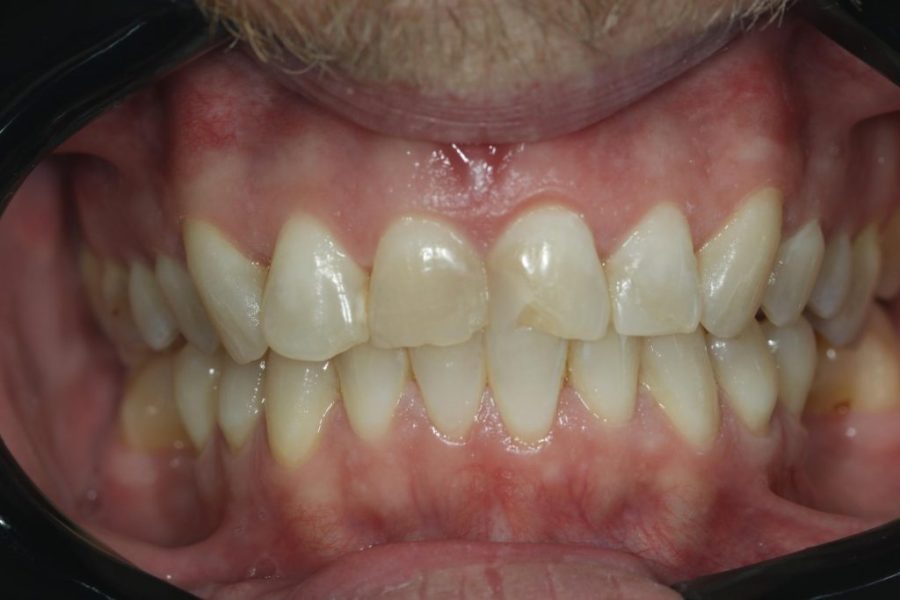

Henry’s Story: A Full Smile Makeover

Henry’s broken teeth were impacting his confidence. With a combination of root canal therapy, laser gum surgery, crowns, and dentures, we restored his smile over four weeks. Now, his family and grandchildren are thrilled with his transformation.